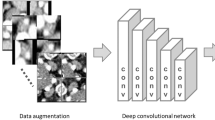

Seven-hundred and three CT images (178 with and 525 without extranodal extension) in 51 patients with cervical lymph node metastases from oral squamous cell carcinoma were enrolled in this study. CT images were cropped to an arbitrary size to include lymph nodes and surrounding tissues. All images were automatically divided into two datasets, assigning 80% as the training dataset and 20% as the testing dataset. The automated selection was repeated five times. Each training dataset was imported to a deep learning training system “DIGITS”. Five learning models were created after 300 epochs of the learning process using a neural network “AlexNet”. Each testing dataset was applied to each created learning model and resulting five performances were averaged as estimated diagnostic performances. A radiologist measured the minor axis and three radiologists evaluated central necrosis and irregular borders of each lymph node, and the diagnostic performances were obtained.